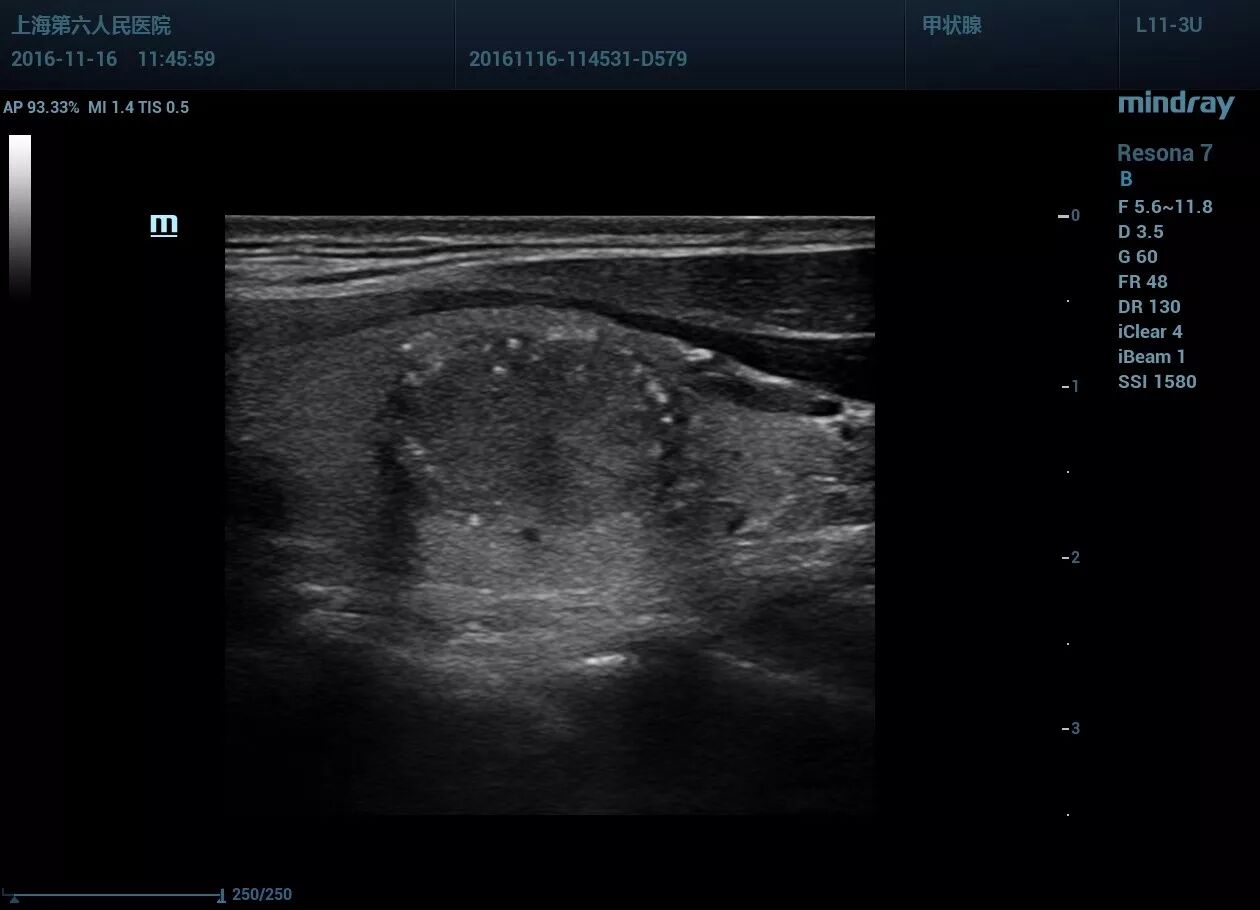

甲状腺左叶见一低回声区,大小约14*13*18mm,形态尚规则,部分边界欠清晰,内见点状强回声。CDFI显示血流信号丰富。左侧颈部VI区一淋巴结见高回声区。